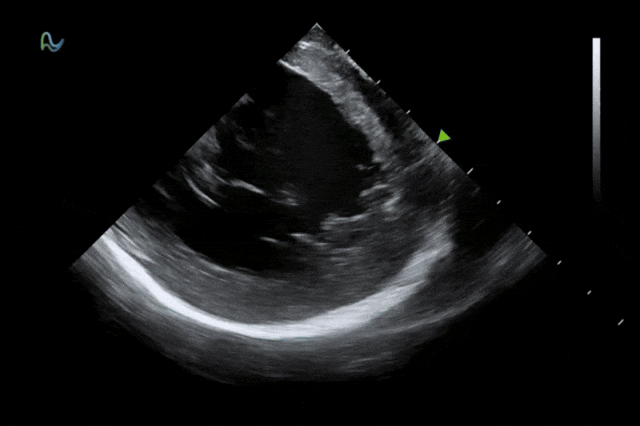

医学成像科学与技术系统全国重点实验室与孵化企业深圳欢影医疗科技有限公司合作研发的"一次性使用心腔内超声诊断导管"正式取得国家药品监督管理局批准上市(三类医疗器械注册证:国械注准20253061587)。作为领域内首款80阵元大孔径高密度探头的心腔内超声导管,其10F/8F双规格设计填补了国内该领域技术空白,为心脏介入手术给予了更精准的国产影像解决方案。

心腔内超声(ICE)被誉为心脏介入手术的"黄金眼",能够顺利获得微创方式实时呈现心脏内部结构和血流成像,为房颤消融、左心耳封堵、先心病介入等手术给予精准成像导航。相较于传统影像手段,ICE具有无辐射、实时成像、操作灵活等显著优势,已成为国际指南推荐的核心诊断技术。

本次获批的ICE导管在全球首次采用了80阵元大孔径高密度探头设计,较传统普通的64阵元产品大幅度提升了成像分辨率、成像深度和图像对比度,可清晰辨识心脏细微结构和血流,为复杂手术给予更可靠的超声成像支持。同时,8F导管凭借更小的外径,显著提升导管顺利获得性和操控性,对病人创伤更小,尤其适合血管条件受限或小心脏患者;10F导管则凭借其优质的成像质量,为复杂心脏介入手术给予精准的影像引导。